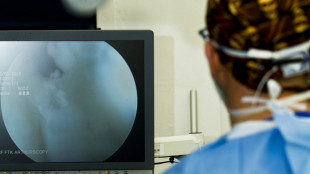

Studio, risonanze fondamentali per i risultati terapeutici contro tumore del retto

Condotto dal policlinico di Chieti.Dati millimetrici decisivi nella valutazione delle cure